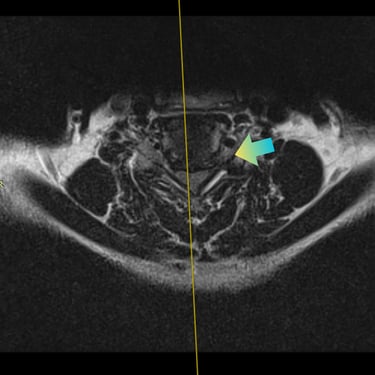

Hernia Cervical con Mielopatía: ACDF con Cage y Placa asistida con Monitoreo Neurofisiológico

La hernia cervical con mielopatía se produce por la compresión de la médula espinal, ocasionando dolor cervical, debilidad, alteraciones sensitivas y trastornos de la marcha. En casos de compromiso neurológico progresivo, la discectomía cervical anterior y fusión (ACDF) con cage y placa es una alternativa quirúrgica eficaz. La cirugía asistida con monitoreo neurofisiológico intraoperatorio permite evaluar en tiempo real la función neurológica, aumentando la seguridad del procedimiento. Este abordaje facilita una descompresión adecuada, estabilización del segmento cervical y favorece una recuperación neurológica segura y progresiva.